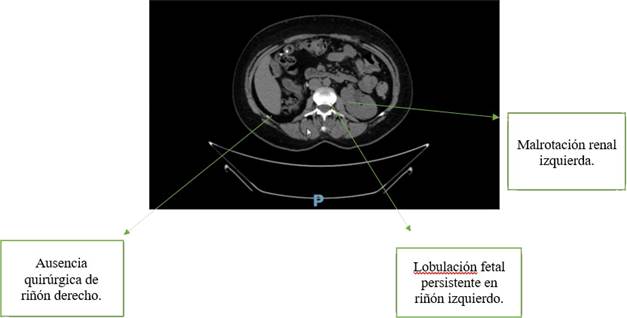

Se practica uroanálisis que evidencia esterasa leucocitaria y nitritos positivos, bacterias en sedimento; gram con bacilos gram negativos y urocultivo con E. coli. Se practica tomografía simple (UROTAC) que evidencia nefromegalia, malrotación izquierda y posible anomalía de fusión, dada su condición de monorrena se practica uroresonancia que confirma nefromegalia, malrotación, lobulación fetal persistente izquierda y ausencia quirúrgica de riñón derecho (Figuras 1 y 2).

Avances en imágenes diagnósticas han permitido clasificar las CAKUT. Sin embargo en este artículo hablaremos con más profundidad de la lobulación fetal persistente que es la presencia de pequeñas hendiduras separadas por surcos entre las pirámides renales. Se presenta en el 4% de la población adulta.

Estas lobulaciones se mantienen durante el periodo fetal pues son indicador importante del desarrollo del feto y se hacen imperceptibles en el tercer trimestre para transformarse en una superficie lisa.6 Esta se deriva de la persistencia durante toda la adultez de una de las doce lobulaciones fetales.7 Se identifica por imágenes como la ecografía de vías urinarias. Estas lobulaciones están en el 8% de riñones derechos, 12% de riñones izquierdos y el resto en ambos riñones de quien las padece.8

También se identifican por imágenes como UROTAC o uroresonancia. Sin embargo, es clave recordar que la lobulación fetal persistente es un hallazgo fortuito en diversos procesos diagnósticos. No causan ninguna afectación a la vida cotidiana por sí mismas, pero su detección alerta sobre la posibilidad de otras CAKUT que si causan complicaciones graves; en este caso hidronefrosis con pérdida renal.

Por otro lado, la paciente tiene asociada malrotación, que es una malformación con una posición anormal con respecto al hilio, característicamente encontramos uréter lateralizado y un hilio anterior con respecto a su posición normal. Puede ser bilateral o unilateral y suele ser hallazgo fortuito. Como hallazgo aislado no tiene relevancia clínica y es asintomática; por lo cual tenemos datos en 1 de cada 2000 autopsias.